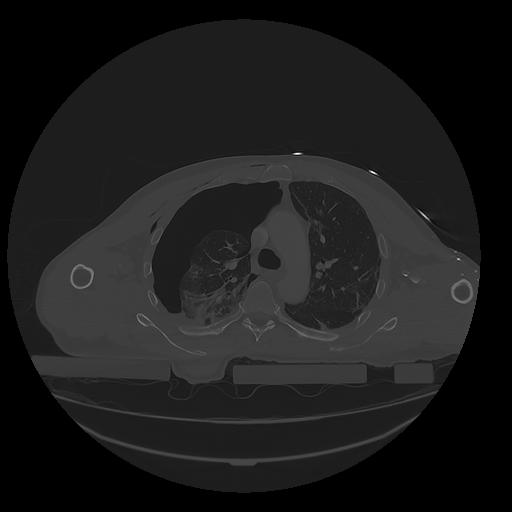

31 PULMON,CE,Vol,1.0,PULMON,,